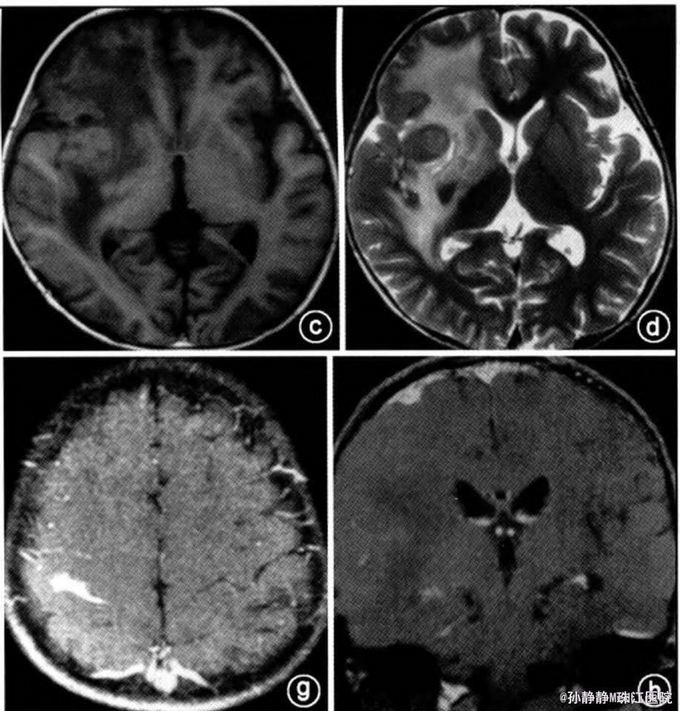

辅查:眼底检查示双侧乳头水肿,颅脑CT示右额叶等密度占位,伴钙化。增强后明显强化,约2厘米。增强MRI T1加权呈等信号,T2 加权等或稍低信号。脑桥、右顶叶也可见病灶,病灶周围可见水肿。

初步诊断:颅内感染性肉芽肿:淋巴瘤?结核?白血病脑病? 处理:考虑患儿有明显颅内压增高症状,行右侧扩大翼点入路开颅手术,切除右额叶明显病变。病理示明显新生血管形成和炎性细胞浸润,部分见组织细胞,核为肾形,疑为朗格汉斯细胞。免疫组化CD68及波形蛋白阳性。S-100及Cd 1a部分细胞阳性。 确诊:颅内朗格汉斯增生症。